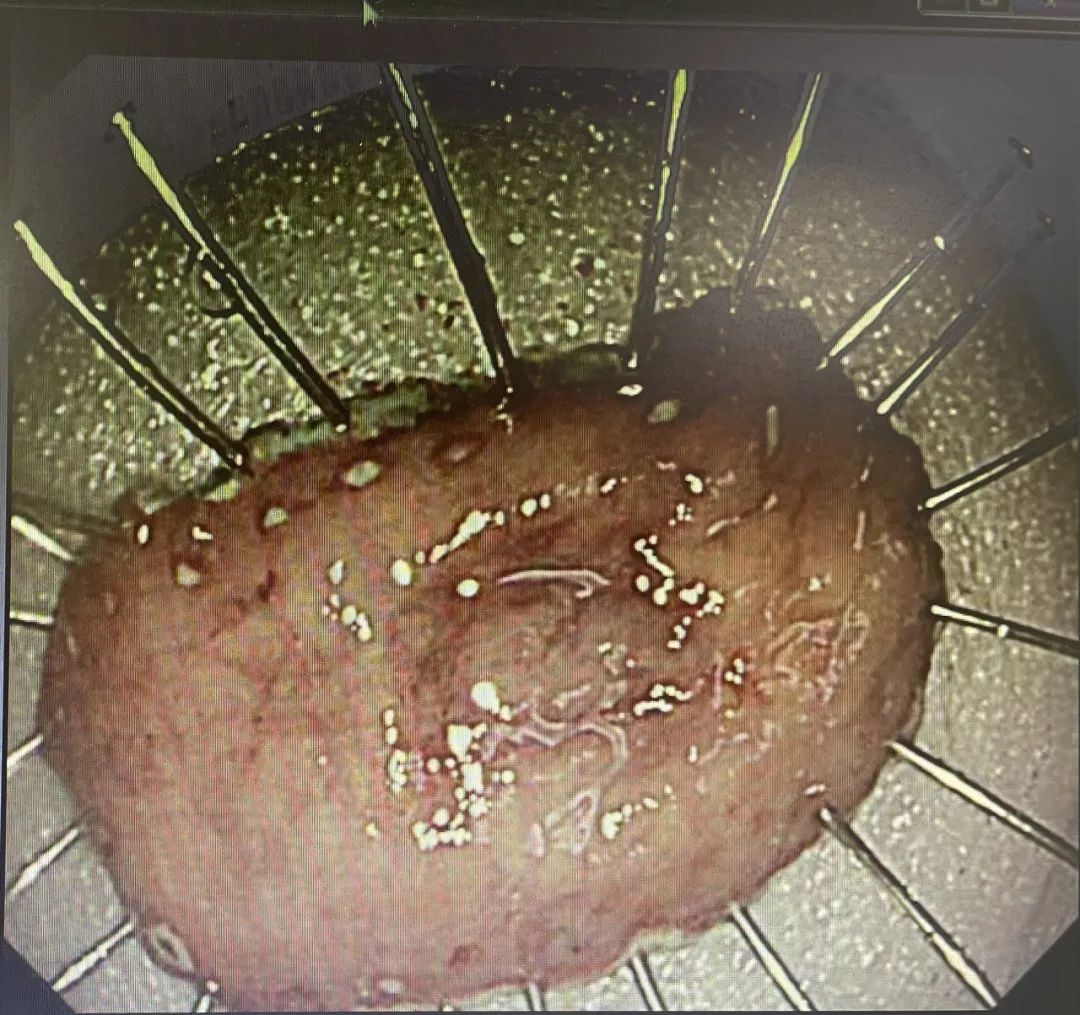

患者,67岁,近一个月因腹部疼痛到院行胃肠镜检查,胃镜提示胃体小弯糜烂性病变,贾傲主任提取组织活检,病理提示高级别上皮内瘤变、局部癌变。根据检查结果诊断:胃恶性肿瘤,行无痛胃镜下内镜黏膜下剥离术(ESD)。

患者,78岁,因“腹部不适”到院行胃肠镜检查,胃镜下显示为萎缩性胃炎,贾傲主任高度怀疑这是一个早期胃癌,根据经验提取组织活检,病理提示粘膜组织部分腺体上皮高级别上皮内瘤变,考虑灶状癌变。跟家属充分沟通后,行无痛胃镜下内镜黏膜下剥离术(ESD)。

患者,60岁,因“便血一周,时有反酸”到院行胃肠镜检查,结合病理提示(胃窦粘膜)高级别腺上皮病变。无特殊禁忌,于是行无痛胃镜下内镜黏膜下剥离术(ESD)。